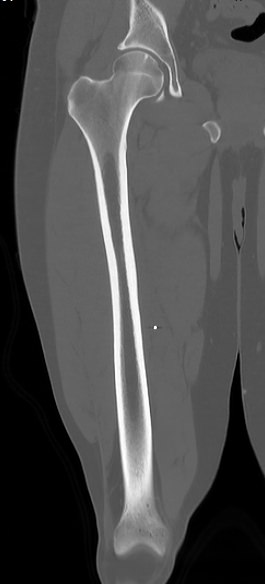

Бедренная кость является наиболее крупной трубчатой костью скелета человека и выполняет основную опорную функцию, обеспечивая прямохождение человека. Головка бедренной кости соединяется с вертлужной впадиной костей таза, образуя тазобедренный сустав, обеспечивающий движения нижней конечности.

Патология тазобедренного сустава и бедренной кости приводит к нарушениям функции нижней конечности и может стать причиной инвалидизации человека. Наиболее распространенными проблемами тазобедренного сустава являются дегенеративно-дистрофические и воспалительные заболевания (артриты, артрозы), травматические повреждения (ушибы, вывихи, переломы). Кроме того, встречаются доброкачественные новообразования и злокачественные опухоли бедренной кости.

Своевременная диагностика и лечение заболеваний бедренной кости и тазобедренных суставов помогает предотвратить негативные последствия для функции нижних конечностей. Наиболее информативным методом диагностики заболеваний данной области является мультиспиральная компьютерная томография, которая относится к лучевым методам исследования.

КТ предусматривает использование рентгеновского излучения, которое хорошо поглощается костной тканью. В результате сканирования и последующей цифровой обработки полученных данных получаются подробные снимки в различных плоскостях, а также трехмерные изображения бедренной кости и тазобедренных суставов, которые можно увеличить и повернуть в разные стороны.

Снимки высокого разрешения позволяют выявить минимальные изменения в костных структурах и окружающих тканях. Мультиспиральная КТ может применяться в экстренных ситуациях для диагностики травматических повреждений бедренной кости и тазобедренных суставов, в частности, при переломах шейки бедра. Кроме того, исследование незаменимо при планировании оперативного вмешательства, а также в послеоперационном периоде для оценки успешности проведенной операции и для отслеживания процесса восстановления.

КТ бедренной кости помогает выявить воспалительные изменения, очаги деструкции костной ткани, доброкачественные и злокачественные новообразования. При подозрении на опухолевый процесс дополнительно применяется контрастное усиление. Для этого пациенту внутривенно вводится контрастный препарат на основе йода, который в большей степени, чем окружающие ткани, поглощает рентгеновские лучи. Поэтому при попадании в опухолевые очаги он обеспечивает их яркую визуализацию на снимках КТ. Методика контрастирования помогает обнаружить опухоли минимальных размеров, определить точные границы опухолевого очага, степень его прорастания в окружающие ткани, эта информация необходима врачу для назначения эффективной тактики лечения.